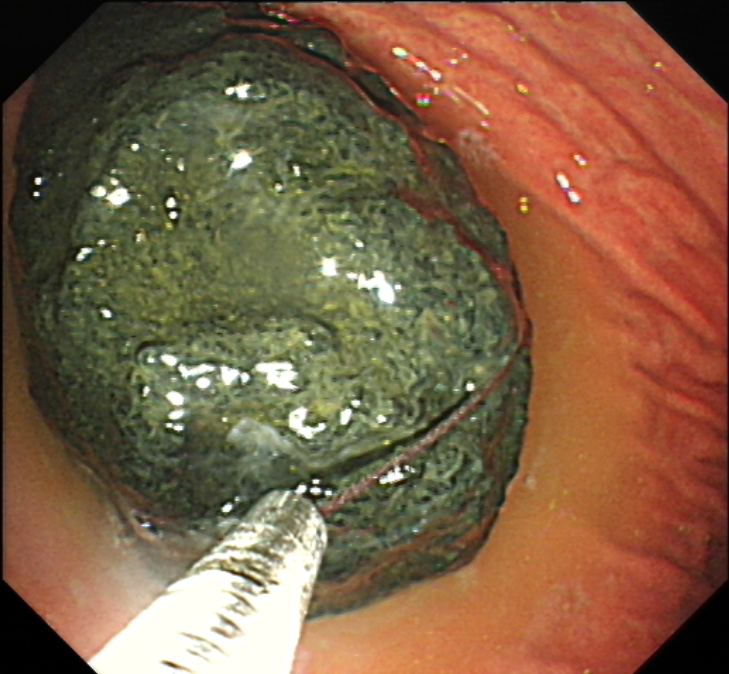

若曾于发病前空腹食用山楂、柿子、黑枣等食物,同时胃镜或者 CT 等影像学检查后,发现胃内结石者,可基本诊断胃石症。

左右滑动查看图片

➋ 胃镜检查及胃镜下碎石术:绞碎后的胃结石小者可自行排出,大的需从胃内取出,以免排入肠道后引起肠梗阻。

-内镜下治疗-